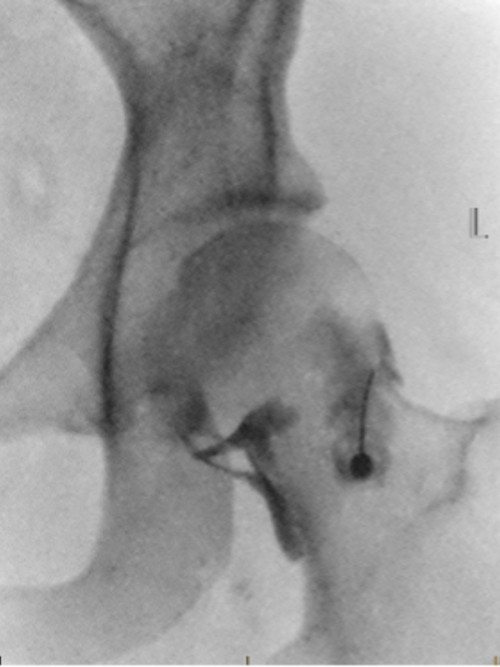

Arthrogram – a procedure to look at a joint, such as your shoulder, hip or knee. Often a dye or contrast will need to be injected into the joint to show more details for a proper diagnosis. These are often done together with an MRI study

Arthrogram

Image credit: Allevia Radiology